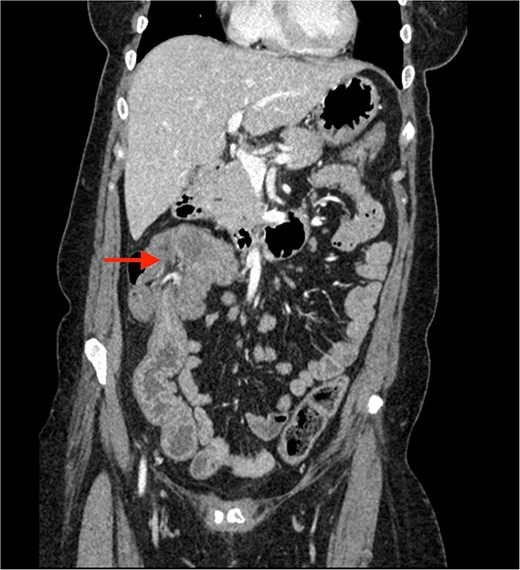

A CECT scan of the abdomen and pelvis revealed circumferential heterogeneously enhancing mucosal wall thickening involving caecum and ascending colon with pericolic fat stranding and ileocolic intussusception along with multiple enlarged heterogeneously enhancing necrotic lymph nodes in right iliac fossa and pericolic region (Figs 1 and 2).

Contrast enhanced CT of the abdomen showing an arrow pointing to the region of ileocolic intussusception.